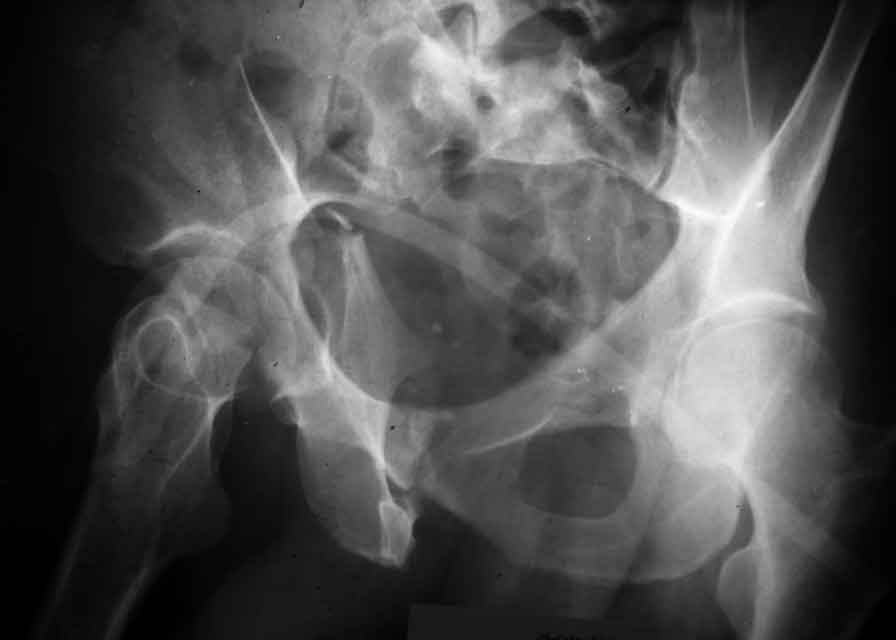

I am sending another iliac view, and a marked version of the AP I already sent. In this AP, the